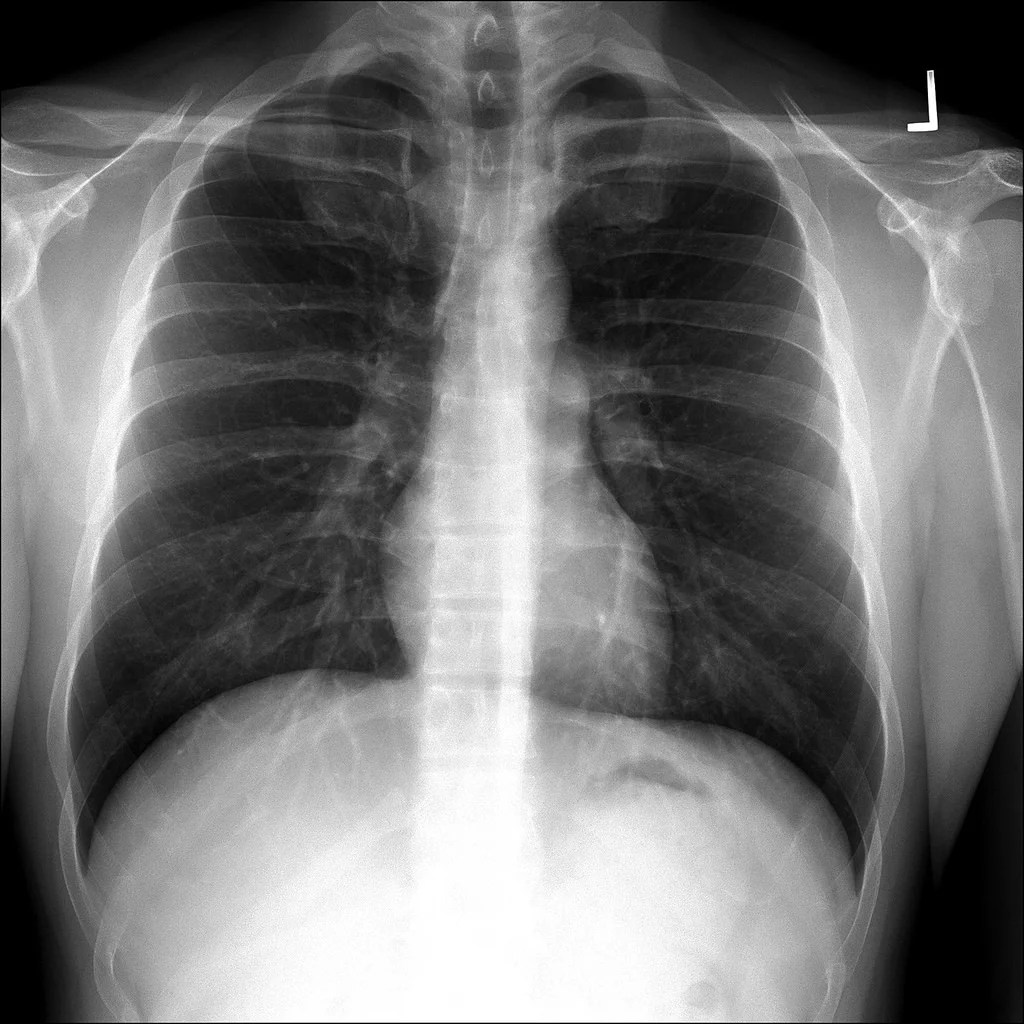

There is no laboratory or imaging test to confirm a diagnosis of costochondritis. The main symptom is pain, but it is also accompanied by a lot of stiffness. Conventional costochondritis treatment and natural remedies may work well together, too.